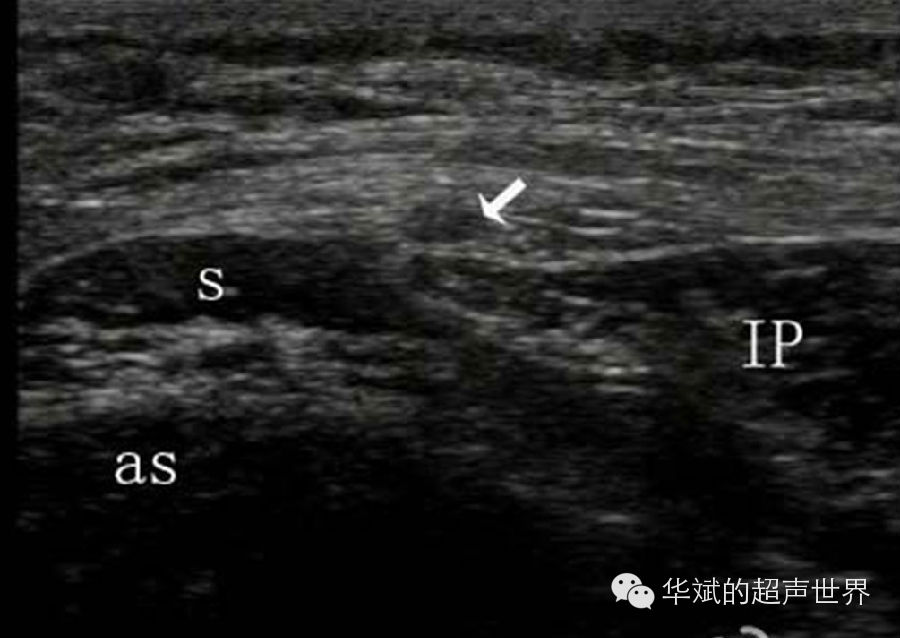

1. 以肌肉作为标志(表二)。外周神经的主干都走形于肌肉筋膜间隙内,因此熟悉每条外周神经毗邻的肌肉结构就可以利用肌肉结构作为神经的标志。例如:枕大神经作为脊神经的分支由椎间孔分出后先下下再向上绕行于头下直肌后方上行。头下直肌是连接枢椎棘突和寰椎横突的一块肌肉,超声检查时非常容易识别,是定位枕大神经的最佳标志(图5)。又如:股外侧皮神经作为腰丛的一支沿盆后壁下行,于髂前上棘水平在缝匠肌和髂肌沟处穿出至皮下。股外侧皮神经是一支细小的皮神经,超声不易直接显示,周围也没有血管伴行,因此在髂前上棘水平显示缝匠肌起点和髂肌即可定位股外侧皮神经(图6)。而肌间沟臂丛神经阻滞则是以前斜角肌和中斜角肌作为标志定位位于臂丛;臀部坐骨神经阻滞则可以以股方肌作为定位标志。

6 股外侧皮神经定位。股外侧皮神经受压水肿(箭头),S:缝匠肌,IP:髂肌